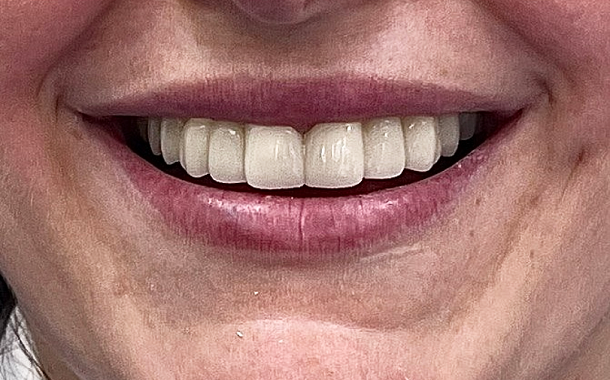

- Максимально точные и эстетичные ортопедические конструкции

- Комфортное и быстрое лечение

- Долговечные результаты

- Индивидуальный подход к каждому случаю